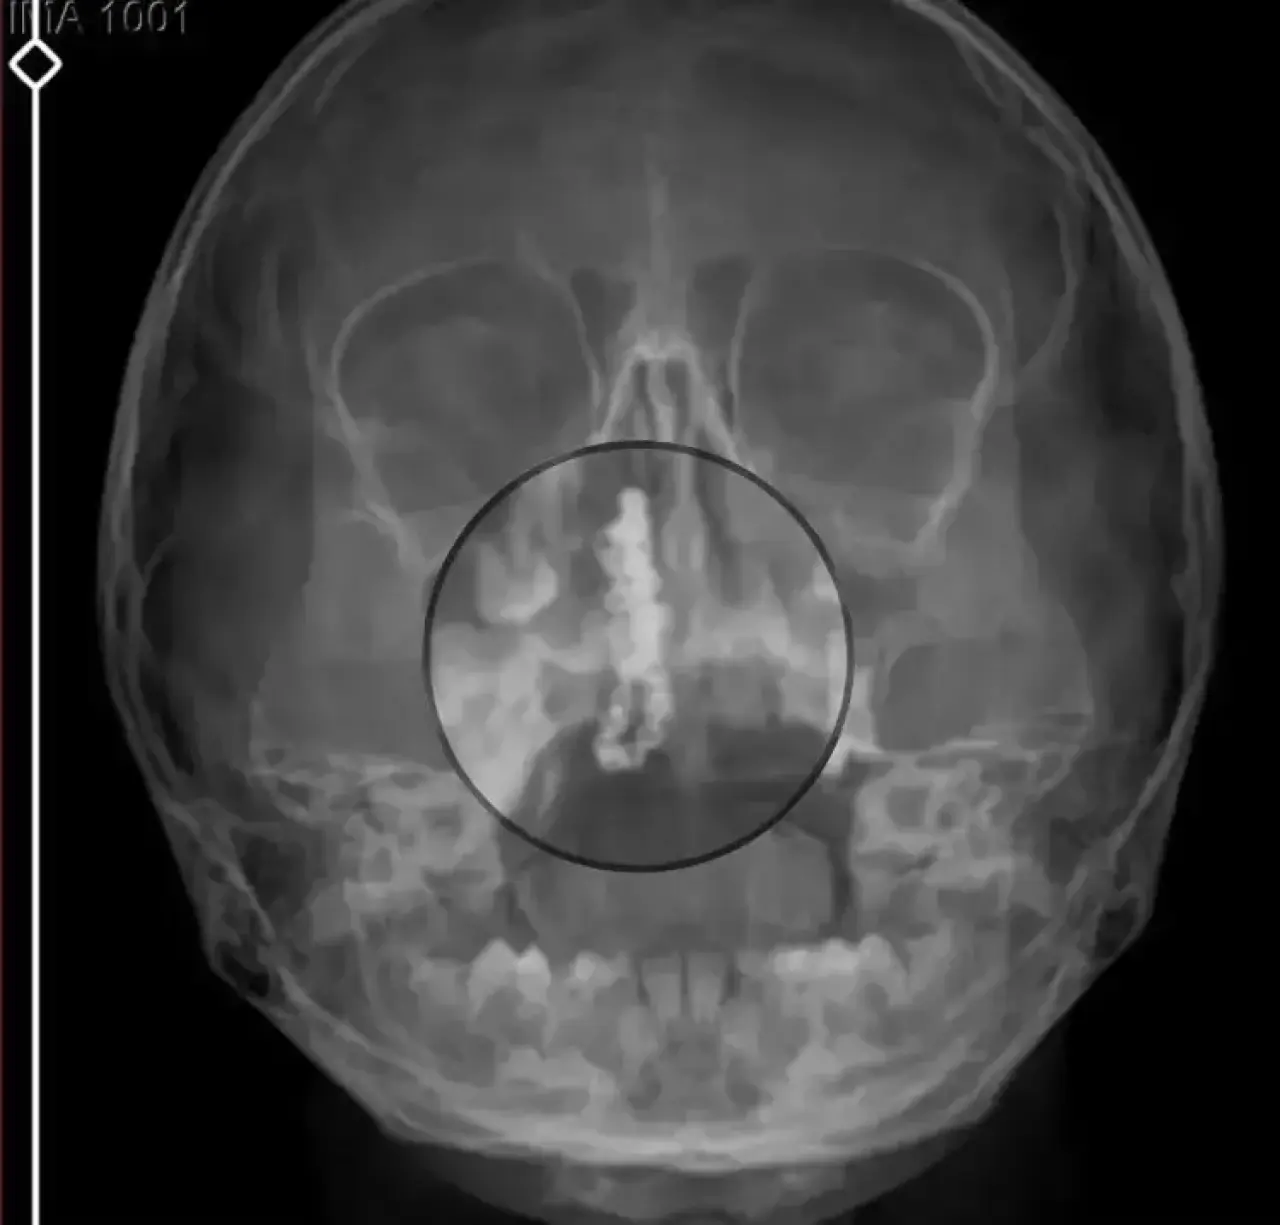

Şikayetlerin sürmesi üzerine aile bu kez Rize Devlet Hastanesi’ne başvurdu. Burada yapılan detaylı muayene ve röntgen incelemesi sonucunda, küçük çocuğun burnunda metal bir yabancı cisim olduğu tespit edildi.

Yapılan değerlendirmeler sonucunda bu cismin bir tırnak makasına ait zincir olduğu ve yaklaşık 2 yıldır burunda bulunduğu belirlendi.